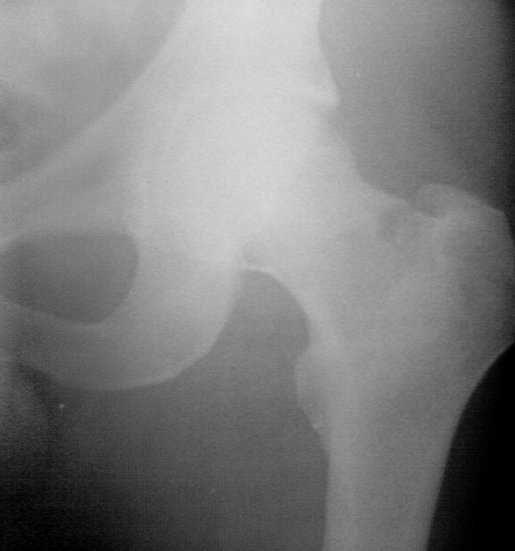

На снимках ложный сустав шейки бедра, несостоятельность фиксации. По положению шурупа можно предсказать ложный сустав, например, если screw backup за кортикальный слой около 15-20 мм, и также изменение угла от первоначального.

№2-3 типичная ошибка несоблюдения концепции параллельности шурупов, нарушение-фиксация поперечным допольнительным шурупом для приближения отломка в результате не сработало метод параллельных шурупов